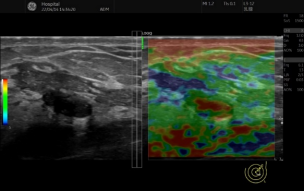

冰晶探头技术可在获得更高分辨力的同时兼顾高穿透力,帮助医师及时观察到脏器的病变。设备搭配的B-Flow™ 类造影血流和MVI 超微细血流成像,对血流显示能力大幅提升, 可捕捉到组织及病灶的细小血管,可观察到血管中较小斑块,提高临床诊疗能力。同时配备应力式弹性成像,对一些器官的结节,可做弹性成像检查,进一步明确肿物性质。

logiq e怎么读【精准医疗 影像先行】五代超高端全身应用彩色多普勒超声诊断仪GE LOGIQ E11在我院投入使用_https://www.jmylbn.com_新闻资讯_第7张

▲新的血流成像技术可清晰包络出甲状腺结节隐藏边界&甲状腺结节内丰富的血流

▲弹性成像显示乳腺浸润性导癌硬度分布